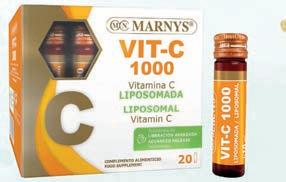

LIPOSOMAL VITAMIN C

20